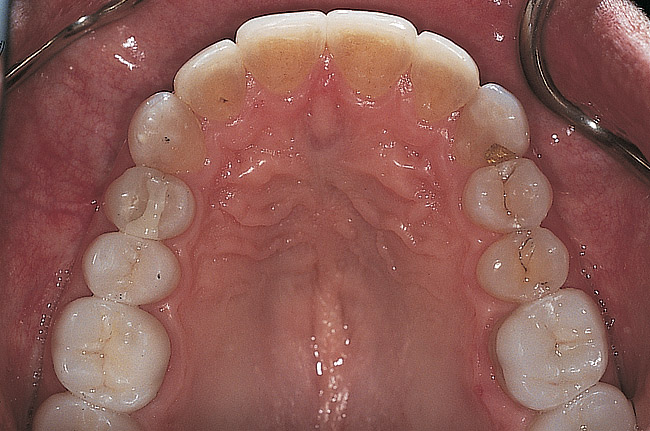

Figure 11  Final occlusal view.

Figure 11